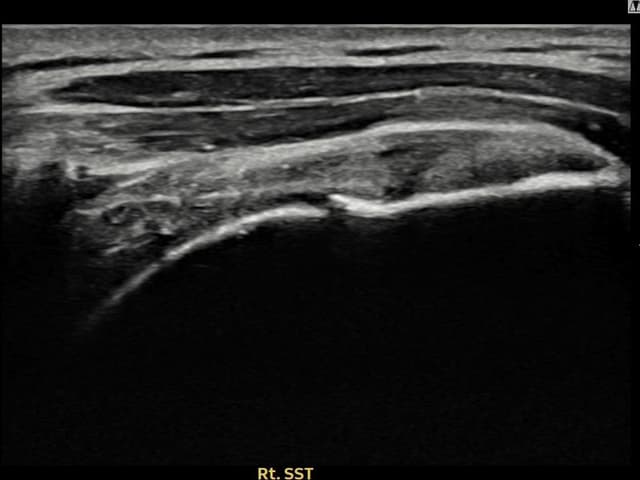

[촬영시기:21.09.27~21.10.07]

[석회분쇄흡입술] 우측 어깨의 야간 통증과 운동 제한으로 수개월간 고통받다 내원한 50세 남성 환자로, X-ray에서 극상근건 내 석회 침착이 확인되어 석회분쇄흡입술을 시행하였습니다.